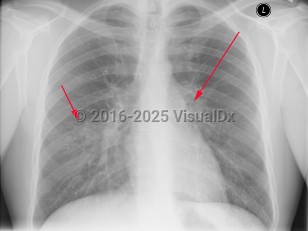

Imaging Studies image of Tuberculosis - imageId=2958883. Click to open in gallery.  caption: 'Frontal chest x-ray with patchy consolidation in the lower lobes bilaterally, right greater than left, (short arrow).  There is also mediastinal adenopathy, (long arrow).'

Frontal chest x-ray with patchy consolidation in the lower lobes bilaterally, right greater than left, (short arrow).  There is also mediastinal adenopathy, (long arrow).